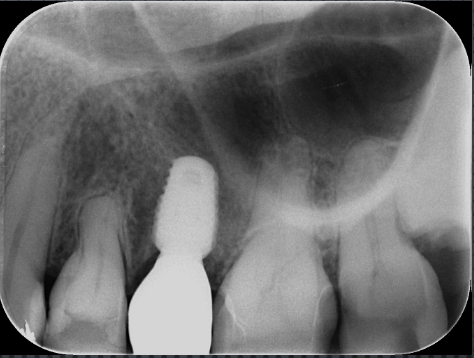

デンタルレントゲン

歯根を取り囲むような黒い影があり、歯根破折を強く疑います。